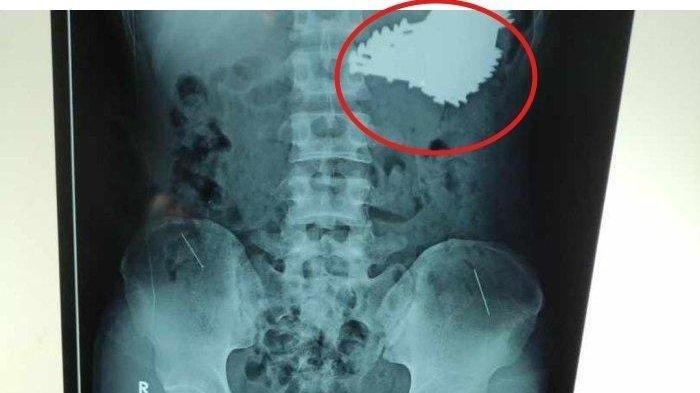

Dari informasi itu, dokter melakukan pemeriksaan radiologi dan pemeriksaan rontgen.

Foto rontgen itu memperlihatkan ada banyak paku berukuran besar yang bersarang di dalam lambung.

Kejadian ini awalnya terungkap dari hasil pemeriksaan rontgen.